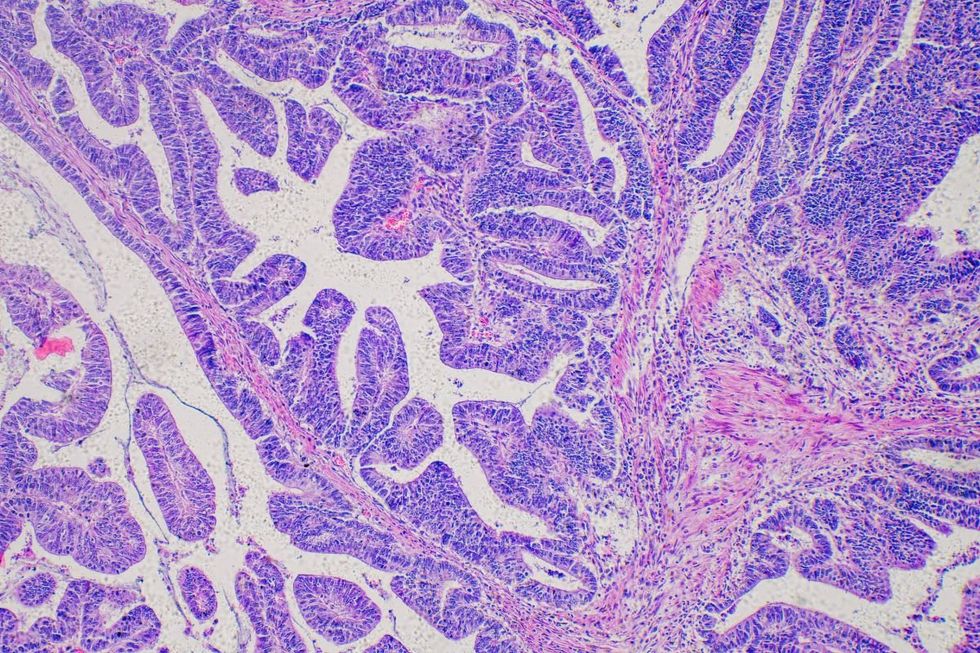

Barrett’s Oesophagus can lead to oesophageal cancer